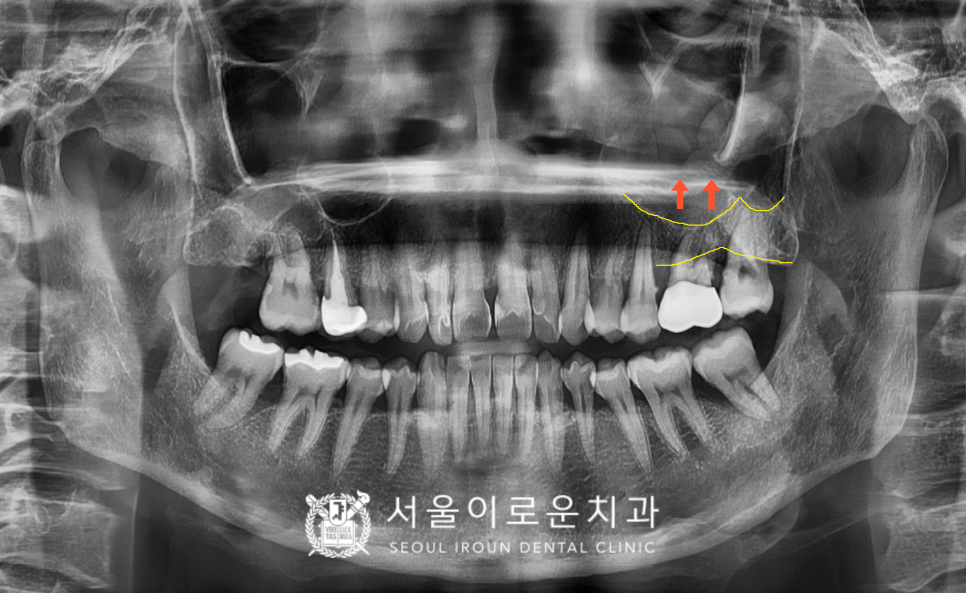

그리고 왼쪽의 경우엔

잇몸뼈와 상악동까지의

수직적인 뼈의 양이 부족하여

상악동 거상술 중

치조정 접근법을 활용하여

임플란트 식립을 진행하기로 하였습니다.

* 위턱 어금니와 광대 사이에

빈 공간으로 이루어진

상악동은 개인에 따라

크기와 모양이 다르며,

상악동과 잇몸뼈 사이에

임플란트를 심을 만큼의 뼈가 없는 경우에는

상악동 점막을 위로 들어 올린 후

잇몸뼈를 채워 넣어

임플란트 식립을 진행하는

상악동 거상술이 선행되어야 합니다.

상악동 거상술 방법 중

하나인 치조정 접근법은

잔존 잇몸뼈에서 상악동까지의

수직적 높이가 3mm 이상인 경우

가능한 상악동 거상술 방법입니다.

위턱 왼쪽 어금니 두 개(#26,27)는

발치 후 염증조직을

깨끗하게 제거하고

발치 후 상악동 거상술(치조정 접근법)을

동반한 임플란트 즉시 식립을

도와드렸는데요.

뼈이식 후 뼈가 빠져나오지 않고

안정적으로 자리 잡고

잘 아물 수 있도록

차폐막으로 덮어

꼼꼼하게 봉합해 드렸습니다.

위턱 오른쪽 두 번째 큰 어금니(#17)는

별도의 뼈이식 없이

임플란트를 식립하였습니다.